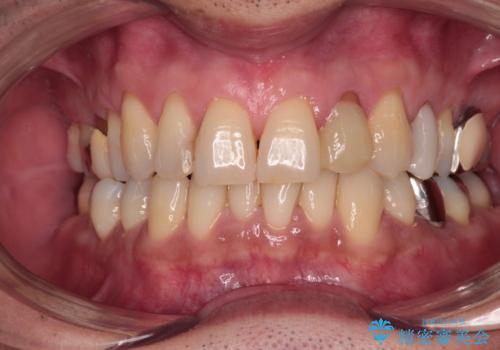

根管治療の土台のまま放置してしまった前歯 オールセラミッククラウンによる補綴治療

- 前歯の根管治療の際に、一時的に見た目を回復したままの状態で放置してしまったとのことで来院された患者様です。

土台の状態は良好であったため、仮歯に置き換えた上でオールセラミッククラウンにて補綴治療を行うこととしました。

見た目の改善はもちろんですが、ものが挟まらなくなったり、舌触りが良くなったりと、口腔内の状態が改善されました。